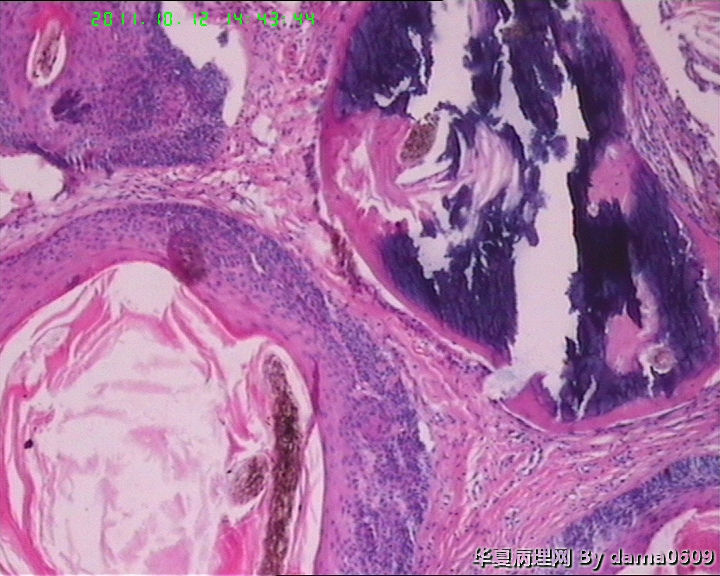

女,42岁,右眼外上方皮下肿物4年。

送检:椭圆形肿物,v:0.5x0.5x0.4cm,实性,灰白色,质软。

• 眼角旁皮下肿物,不会了啊!!图4

图4

毛发腺瘤

脂溢性角化病伴局灶钙化及色素沉积.

皮肤及附属器的肿瘤学生见得少,这一例发病部位和大体上符合“毛发上皮瘤”,但静下上好像要求由两层基底样细胞条索样排列和增生的间质构成,具体记不清了,也不知道对不对,我这例不见那样的典型结构啊!!

镜下大部分都是毛囊结构,要考虑毛囊痣。